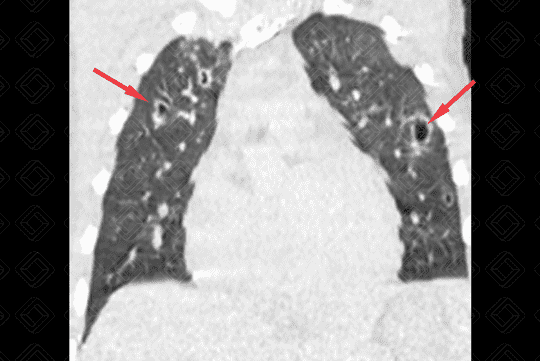

Descrição da lesão: Tomografia computadorizada do tórax (imagem axial e reformatação coronal) demonstrando opacidades nodulares bilaterais, esparsas e predominantemente periféricas, em vários estágios de escavação (setas vermelhas).

• Tomografia computadorizada do tórax: Nódulos em diferentes estágios de escavação, sendo mais numerosos na periferia dos pulmões e nos lobos inferiores. Podem ser observadas ainda consolidações geralmente subpleurais e cuneiformes.